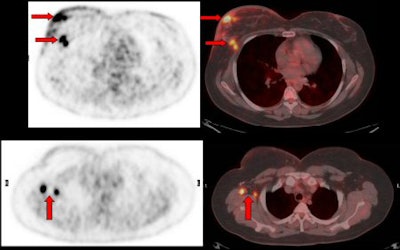

![]() |

| Image of a 47-year-old woman with breast carcinoma shows how PET/CT demonstrated multifocal right breast disease (horizontal arrows) and right axillary lymph nodes metastases (vertical arrows). |